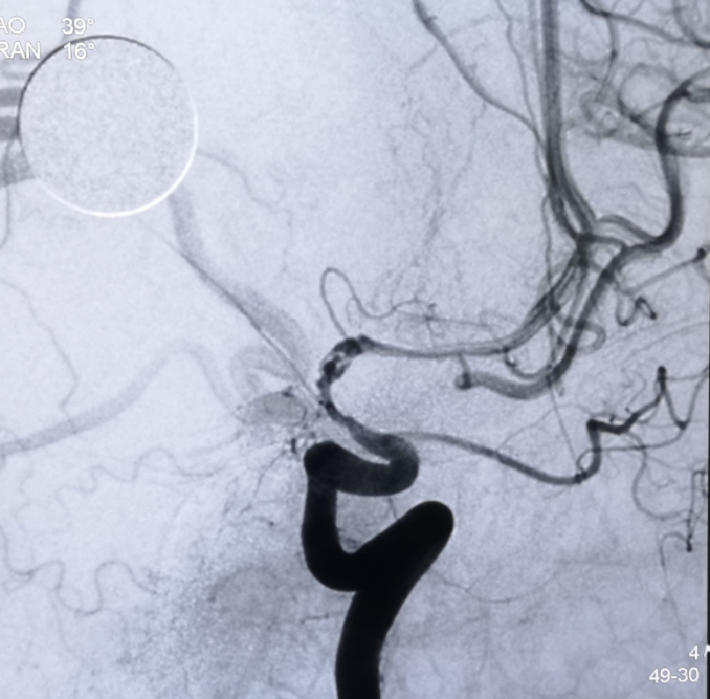

此次入院后,即予行全脑血管造影术,示左侧颈内动脉虹吸段重度狭窄。予患者家属充分沟通后,进一步行左侧颈内动脉虹吸段狭窄球囊扩张+支架植入术。

DSA

考虑狭窄段为夹层样改变,多角度导引导管造影,以更清晰地区分真假腔,选择最佳工作角度

--DSA显示左侧颈内虹吸段狭窄约72%。前交通开放,右侧大脑前动脉通过前交通动脉向左侧大脑前动脉、大脑中动脉供血区有代偿供血。